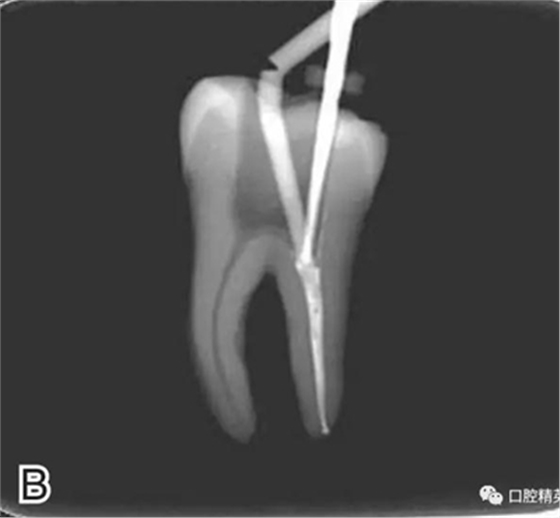

3、試尖

選擇非標(biāo)準(zhǔn)牙膠尖(如0.04、0.06 錐度牙膠尖)作為主尖,型號(hào)一般與根管預(yù)備最大號(hào)的器械型號(hào)一致,能到達(dá)距根尖0.5~1 mm 處,主尖尖段與根管壁緊密接觸。拍試尖X 線片進(jìn)行確認(rèn)(圖3)。

圖3 試尖,A.試主尖 B.拍試尖X片